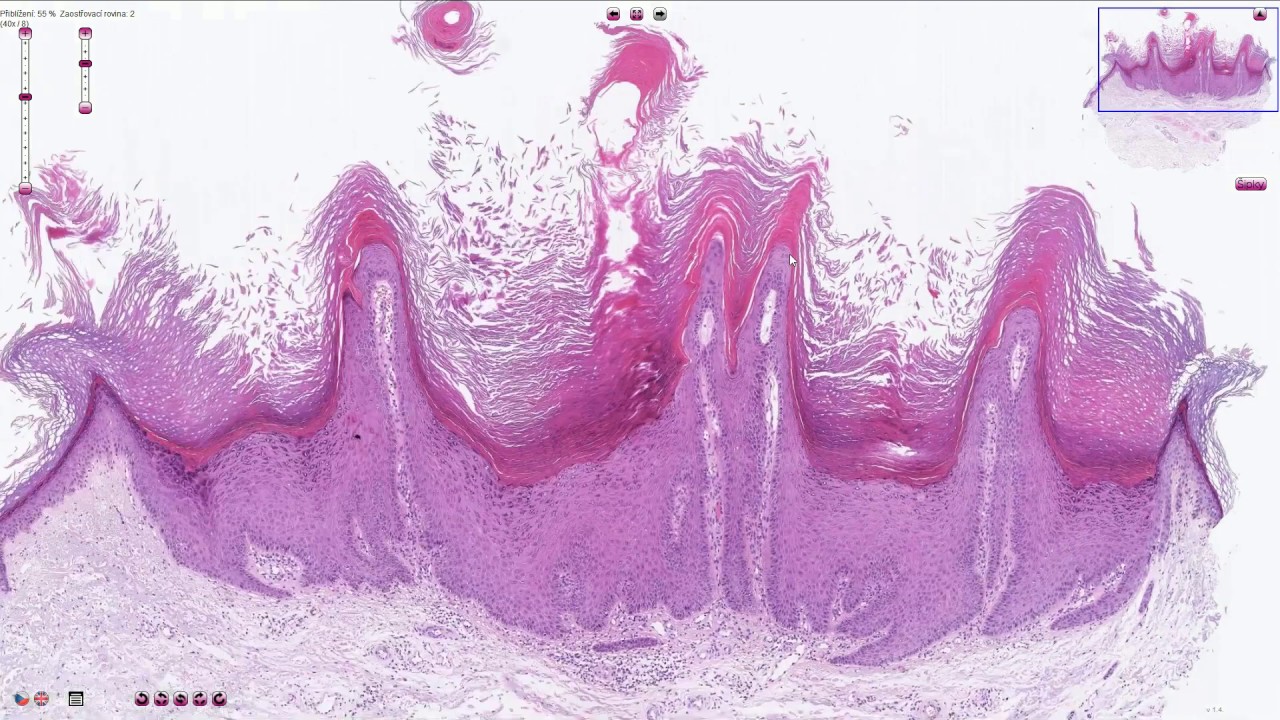

Бородавка под микроскопом (Verruca Vulgaris vs. Патология себорейного кератоза)

Описание: Быстрый взгляд на симпатичную бородавку в сравнении с соседним себорейным кератозом.